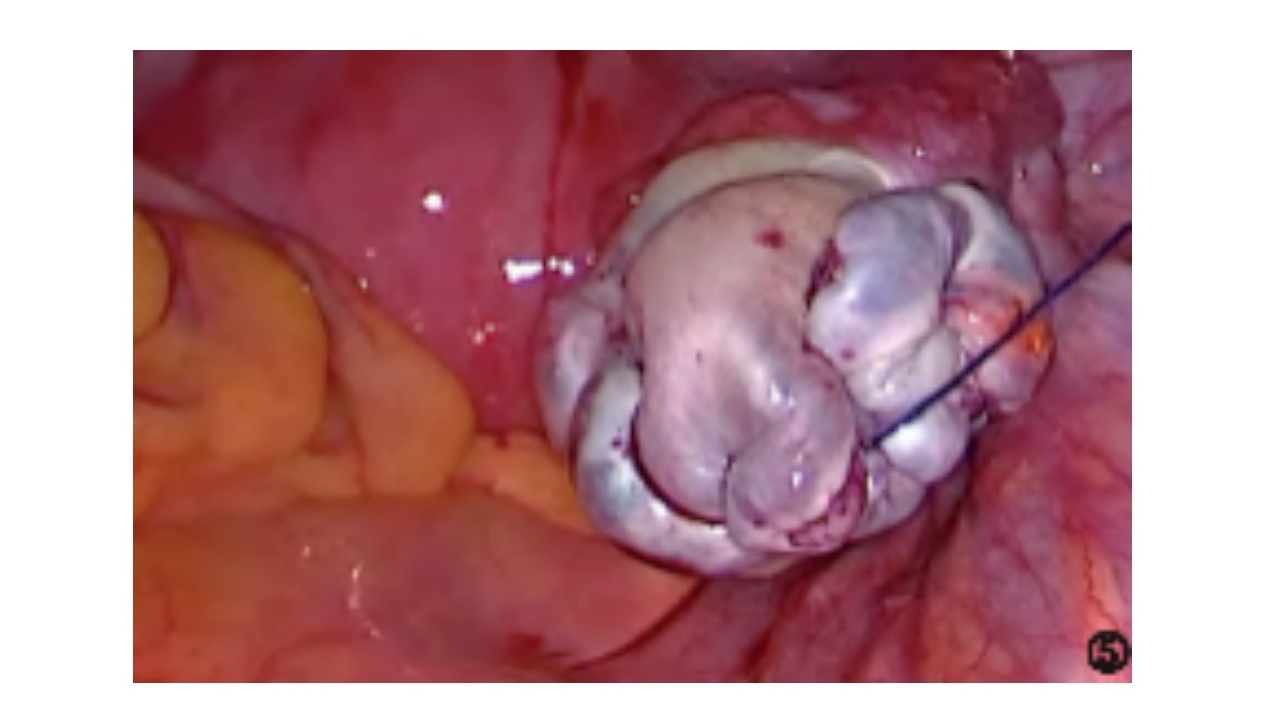

闭合死腔和卵巢成形,达到止血和减少渗血的目的,且不能包埋卵巢皮质,以免影响排卵。

采用2/0-3/0可吸收缝线荷包缝合、连续缝合或“8”字兜底缝合,也可采用2/0倒刺线连续缝合。按照自固有韧带侧至骨盆漏斗韧带方向先深后浅的原则缝合卵巢创面,缝至骨盆漏斗韧带侧顶端后调转反向缝合,线尾需保留足够长度以备最后打结。

▪缝合的左右两侧卵巢组织应尽量厚薄对称,缝线尽量包埋在卵巢皮质内,并将线结打在创面内,以降低术后粘连概率。

▪缝合卵巢应与输卵管走行平行,以免导致输卵管扭曲。

▪缝线的松紧度应以切口边缘紧密贴合为准,不宜过紧或过松,确保缝合后的卵巢表面光滑。